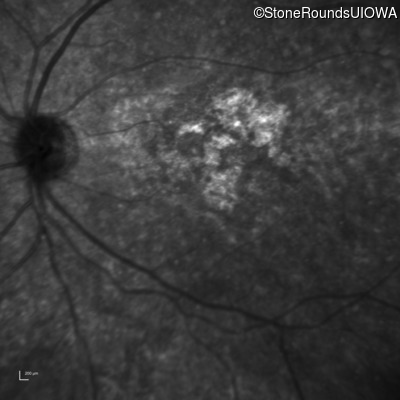

Age at visit: 26 years

OD OS